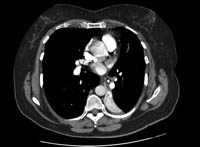

Em crianças, a TC com multidetectores (TCMD) com broncoscopia virtual pode ser usada para diagnosticar a aspiração de corpo estranho e para determinar a localização exata da obstrução. Tem sensibilidade de 92% a 100% e especificidade de 80% a 85%.[40][41] Os falso-positivos ocorrem por causa de secreções e tumores endobrônquicos. Em adultos, a broncoscopia deve ser realizada subsequentemente para confirmação, ou para diagnosticar as causas alternativas de obstrução das vias aéreas.[Figure caption and citation for the preceding image starts]: TC do tórax com material de contraste intravenoso mostrando colapso total do lobo inferior esquerdo com um objeto radiopaco dentro do brônquio principal inferior esquerdo, circundado por um halo de arBMJ Case Reports 2008 (doi:10.1136/bcr.06.2008.0013). Copyright 2008 BMJ Group Ltd [Citation ends].

o corpo estranho pode ser observado no lúmen das vias aéreas; achados comuns indiretos incluem atelectasia, hiperlucência e condensação lobar